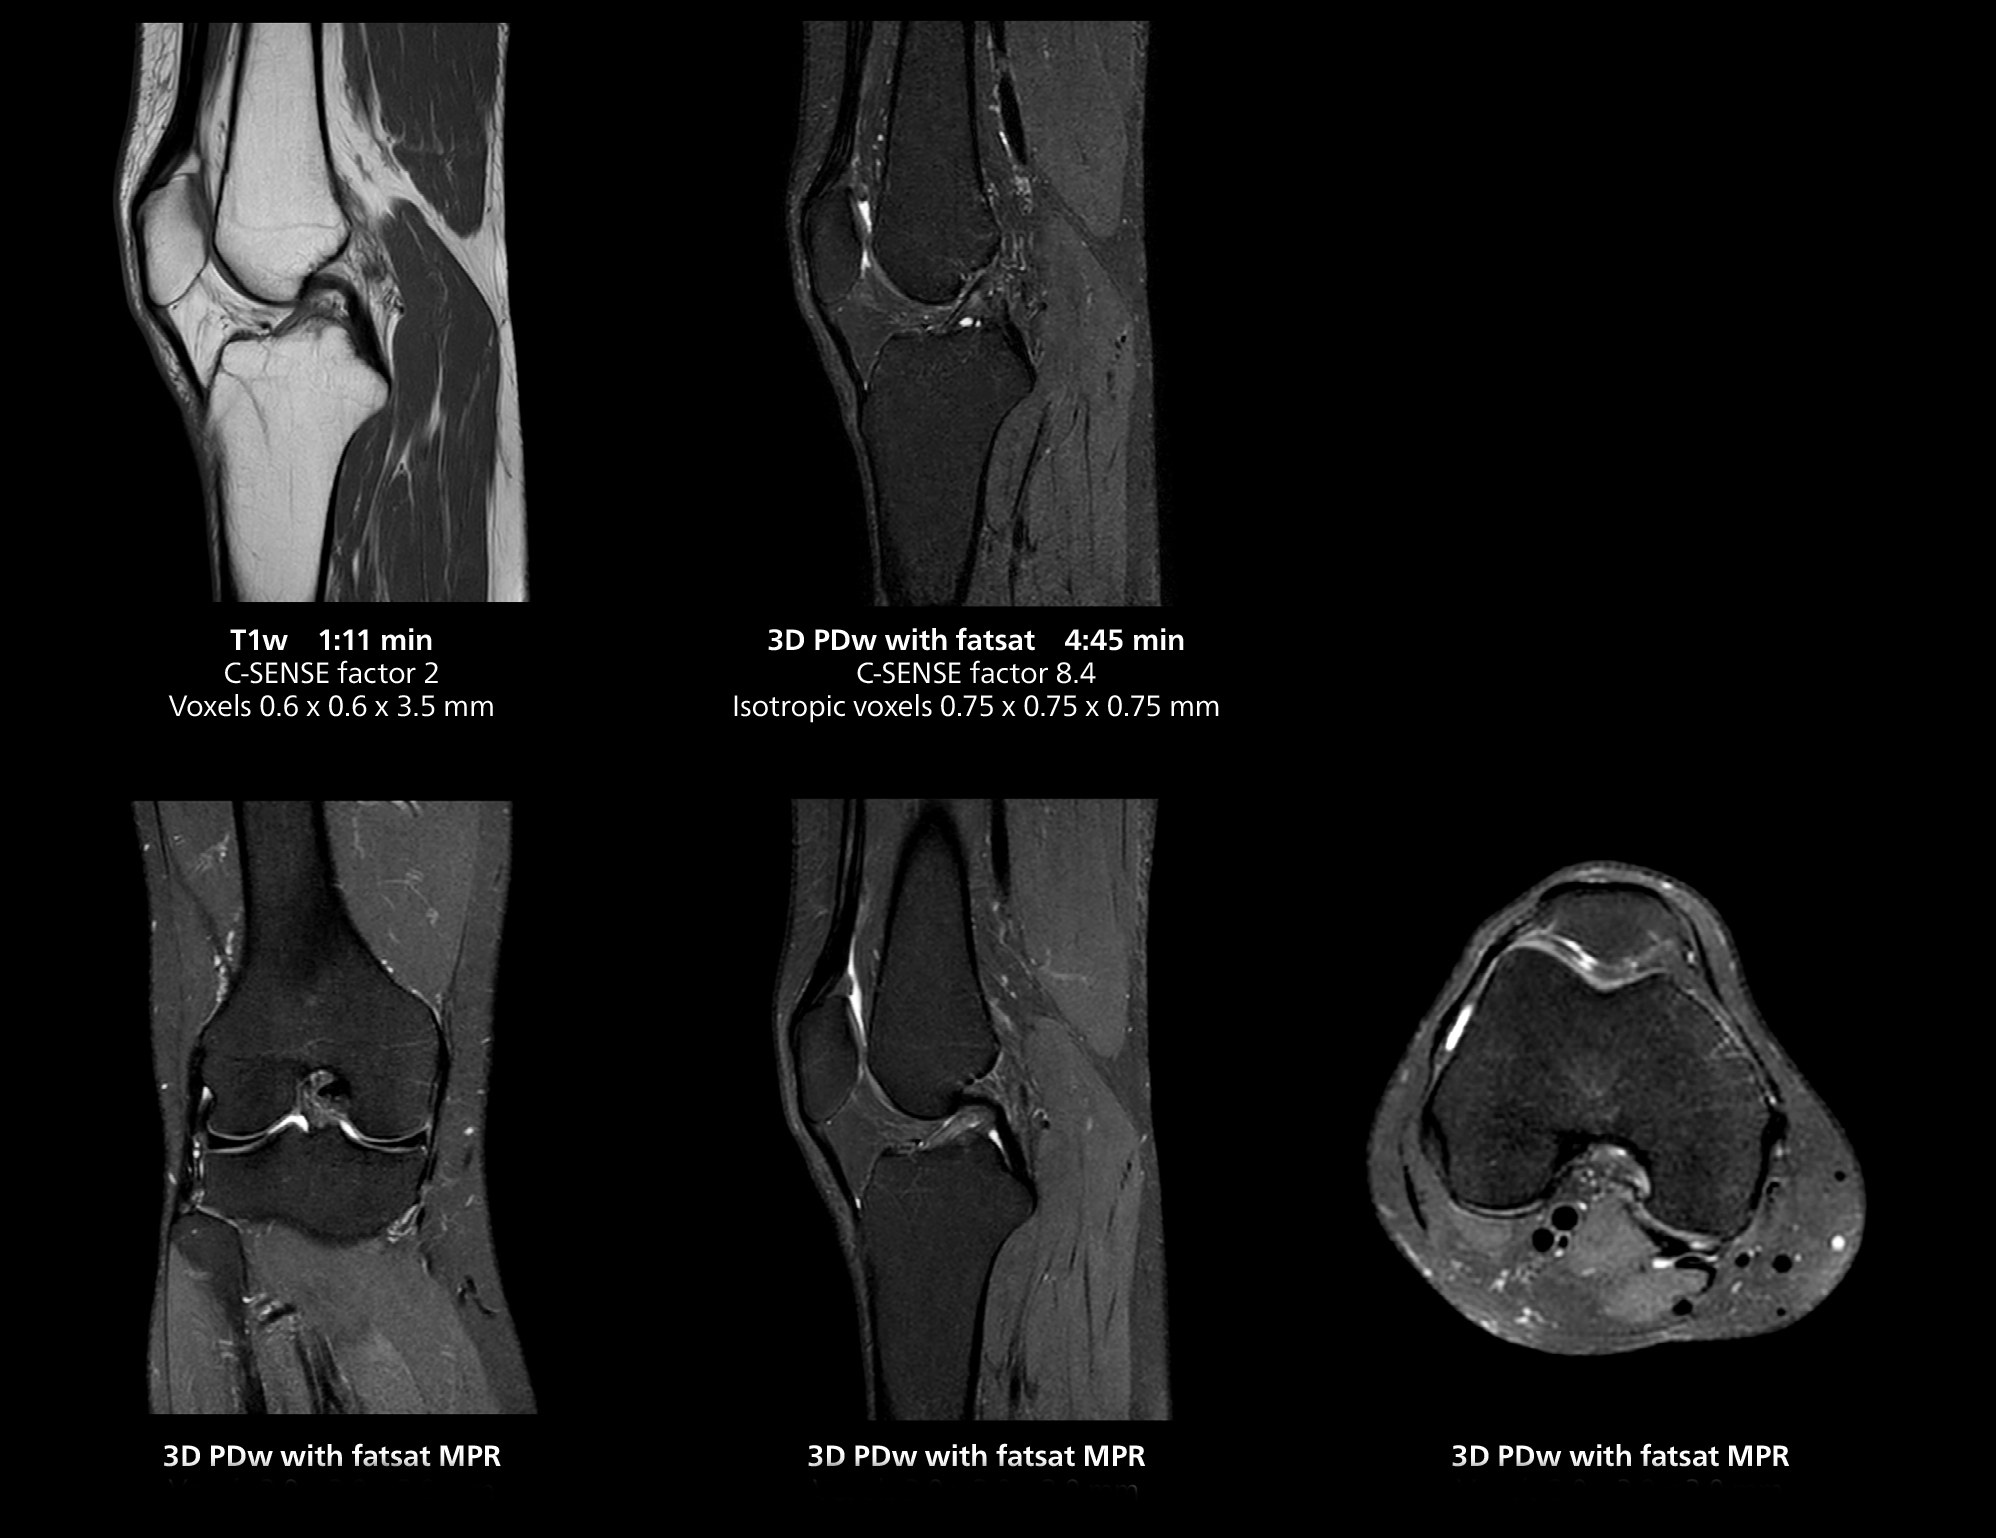

3D knee imaging

The isotropic high resolution 3D sequence in this MRI case allows for reformatting to obtain other orientations with high quality. Acquired on the MR 5300 system.

According to Dr. Gellée, the hospital conducts an average of four studies each hour, totaling about 40-45 patients per day on their MR 5300. Studies are read by approximately 50 radiologists in the Bordeaux area. Dr. Gellée is especially satisfied with the image quality of the MR system. "I obtain higher image contrast and more anatomical precision than I was used to,” she says. “When I am able to choose, I request that studies be done on this system, because I get better anatomical image quality. For example, in the knees, I can get great images of the meniscus. To me, it looks as pretty as 3T.”

“We have more speed in 3D sequences,” Dr. Gellée states. “With Compressed SENSE, we can replace two or three 2D scans withone high-quality 3D scan. High quality additional orientations are then obtained by post-processing of the 3D data set, thus saving scanning time.”